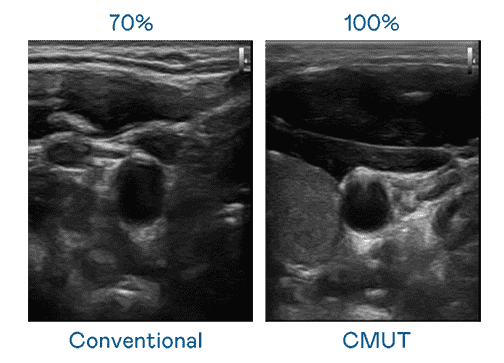

CMUT 技术是一种用电容式微机电元件来产生超音波讯号的技术。。。与传统 PZT 压电式技术相比,,,,CMUT 频宽增加 30%,,,更宽频的超音波讯号让影像解析度大幅提升,,,是实现高影像品质医疗超音波扫描、、、促进精准医疗发展的关键技术。。

大频宽带来超清晰影像

超音波影像的解析度高低,,首先取决于探头能发出的讯号频宽。。。。尊时凯龙 CMUT 可提供高清晰的超音波讯号,,,,提供高频宽、、高灵敏度、、、影像纹理细节更高的超音波影像,,,,协助医护人员缩短影像判读时间及利用精准的医疗影像进行诊断。。